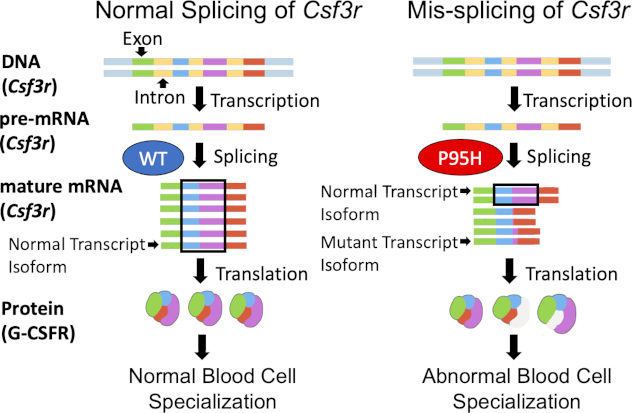

Targeted isoform-specific analysis of Csf3r alternative splicing in splicing factor mutant myeloid cells

Csf3r is alternatively spliced in SRSF2P95H mutant blood cells in a cell-type specific manner.

Posted by buchanle on Tuesday, April 30th, 2024 in May 2024, Csf3r, Mis-splicing, myeloid malignancies, SRSF2P95H